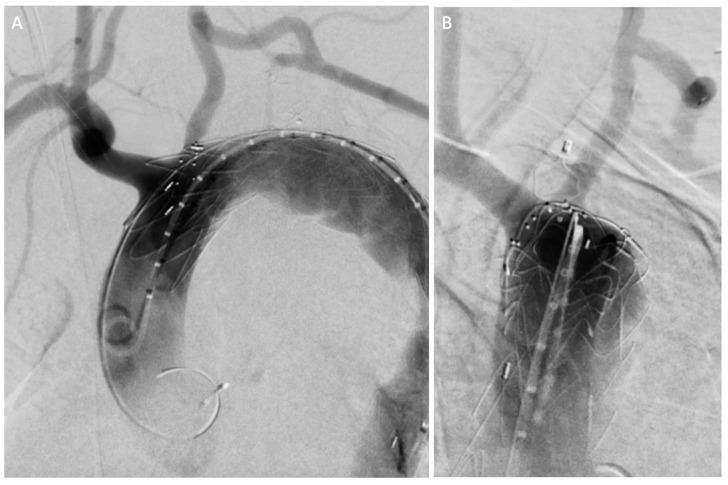

Grade I-II blunt traumatic aortic injuries (BTAIs) are typically managed conservatively, but their long-term progression is poorly understood. Chronic pseudoaneurysms may develop years after the injury, often remaining asymptomatic and being incidentally diagnosed. Two cases of post-traumatic aortic pseudoaneurysms, detected 20 and 25 years following conservatively managed BTAIs, are reported. Additionally, a comprehensive review of all post-traumatic pseudoaneurysms reported in the MedLine (PubMed.gov, U.S. National Library of Medicine, National Institute of Health) database between January 1984 and December 2024 was performed. Both our patients underwent successful hybrid procedures, with no complications at the 1- and 4-year follow-ups. Our literature review identified 37 patients across 22 studies, with 32.4% presenting asymptomatically or incidentally diagnosed through routine imaging, between 1 month and 50 years after the initial trauma. In 37.8% of cases, the patients underwent open or endovascular repair. This case series and literature review emphasize the importance of long-term follow-up for patients with conservatively managed BTAIs, as chronic complications such as aortic pseudoaneurysms can arise decades later. Continuous surveillance is critical to ensure early detection and management.

I-II级钝性创伤性主动脉损伤(BTAIs)通常采用保守治疗,但其长期进展情况尚不清楚。慢性假性动脉瘤可能在损伤数年之后形成,常常没有症状,而是在偶然检查时被诊断出来。本文报告了两例在保守治疗BTAIs后20年和25年发现的创伤后主动脉假性动脉瘤病例。此外,还对1984年1月至2024年12月期间MedLine(美国国立医学图书馆、美国国立卫生研究院的PubMed.gov)数据库中报告的所有创伤后假性动脉瘤进行了全面综述。我们的两名患者均成功接受了杂交手术,在1年和4年随访时均无并发症。我们的文献综述在22项研究中确定了37例患者,其中32.4%在初次创伤后1个月至50年之间没有症状或通过常规影像学检查偶然被诊断出来。在37.8%的病例中,患者接受了开放手术或血管腔内修复。这个病例系列和文献综述强调了对接受保守治疗的BTAIs患者进行长期随访的重要性,因为诸如主动脉假性动脉瘤等慢性并发症可能在数十年后出现。持续监测对于确保早期发现和治疗至关重要。